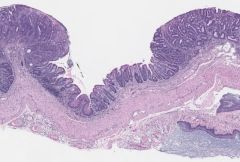

The research, published Aug. 18 in Nature, focused on the effect of a high-fructose diet on villi, the thin, hairlike structures that line the inside of the small intestine. Villi expand the surface area of the gut and help the body to absorb nutrients, including dietary fats, from food as it passes through the digestive tract. The study found that mice that were fed diets that included fructose had villi that were 25 percent to 40 percent longer than those of mice that were not fed fructose. Additionally, the increase in villus length was associated with increased nutrient absorption, weight gain and fat accumulation in the animals.